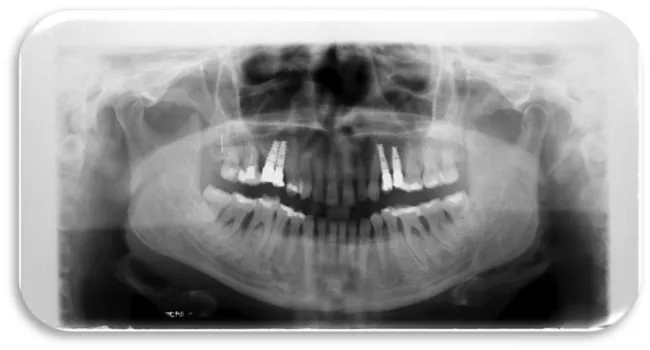

The fourth clinical case was a 51 year old male patient. He is an active cigarette smoker and has a cardiovascular disease. A dental implant is placed in the upper right quadrant, the exact position is 14. The role of dental implant is to compensate the upper first right premolar. After 12 months from the dental implant placement, a control panoramic image was made in order to see the condition of the dental implant. In the orthopantomographic image below (Figure 26), the extensive bone resorption was noted in both jaws, which is particularly expressed in the maxilla.

In the upper left quadrant on posterior region, one more titanium dental implant was placed, which compensates the lost first molar. In the lower left quadrant on the posterior region, another dental implant was placed instеad of the lower first natural molar. After 9 months a control panoramic X-ray was made in order to follow the condition of the bone tissue in the both jaws. From the figure 27 it’s evident that bone resorption is more expressed in maxilla than in mandible. The larger bone defect was noted in the upper posterior right quadrant, where two dental implants are placed next to each other.

The sixth clinical case was a 29 year old female patient with excellent health condition. Three dental implants were placed in the lower right quadrant. Dental implants compensate previously lost first and second permanent molars. On the panoramic image below (Figure 28), could can be seen that bone resorption was more pronounced in the mandible, especially in the lower right posterior quadrant, than in the maxilla. The panoramic record was done after 11 months of dental implants placement (Figure 28).

The seventh clinical case was male 33-year-old patient with good health condition and without any illness. He received dental implants in maxilla both in the right and the left posterior quadrant, 10 months ago. On the panoramic X-ray image marginal bone resorption changes were present in both jaws (maxilla and mandible). Bone resorption was observed on mesial and distal side from dental implants, also horizontal type of resorption is present (Figure 29).

The eleventh clinical case was a 53 year old male patient with cardiovascular disease, but well treated by cardiologist He received 5 titanium dental implants. He received three titanium dental implants in maxilla in the left posterior quadrant and two titanium dental implants in mandible, in the right posterior quadrant half-year ago. Due to patient’s inadequate maintenance of the oral hygiene, during consecutive 6 months, inflammatory changes and bleeding from the gums occurred during the act of mastication. After the RTG examination, resorption of the bone tissue in both jaws was detected. Bone destruction is more pronounced in the maxilla than in the mandible (Figure 35).